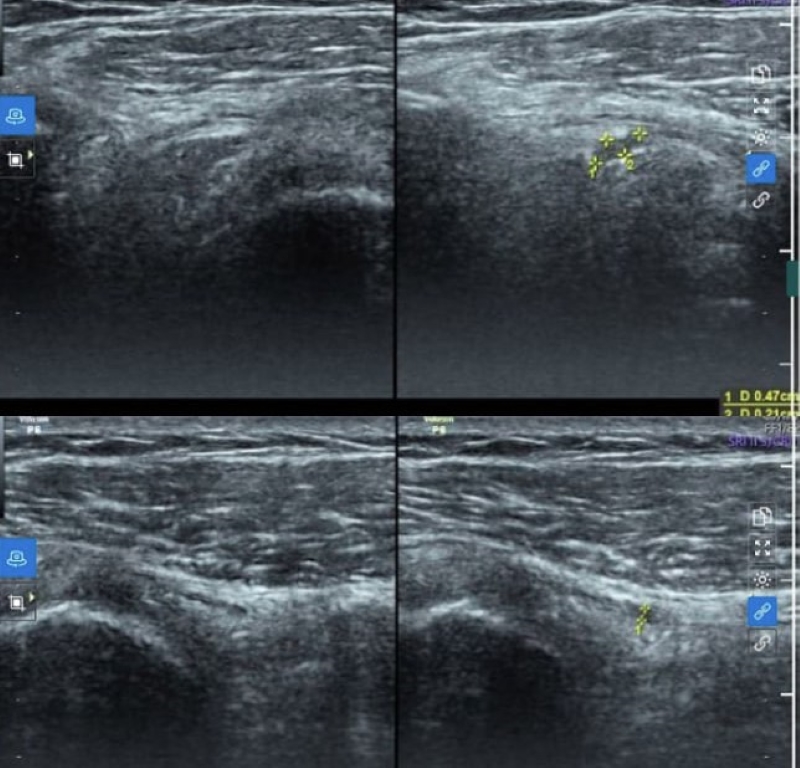

Tại đây, bác sĩ tiến hành thăm khám và chỉ định các kỹ thuật cận lâm sàng cần thiết phục vụ chẩn đoán. Đáng chú ý, trên hình ảnh siêu âm khớp vai phải bằng đầu dò tần số cao cho thấy tình trạng rách bán phần gân cơ trên, ít dịch trong túi hoạt dịch dưới cơ Delta.

Hình ảnh tổn thương được phát hiện trên siêu âm khớp vai

Chẩn đoán xác định, tình trạng của bác M. là rách bán phần gân trên gai, viêm bao thanh dịch dưới cơ Delta vai phải. Bệnh nhân được chỉ định điều trị bằng phương pháp tiêm huyết tương giàu tiểu cầu vị trí rách gân trên gai và bao thanh dịch dưới cơ delta vai phải dưới hướng dẫn siêu âm.